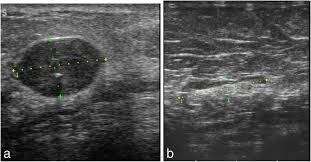

17 years experience general surgery. Solid lesions can be a little brighter or darker than the surrounding tissue, and the way to evaluate these on ultrasound is to look closely at the margins or the outer edges of the nodule. A breast ultrasound is a painless procedure that uses sound waves to make images of the inside of your breast. What does breast cancer look like on a mammogram? Dcis on mri may create an area of irregular enhancement of the mri dye into the breast. Breast cancer is among the most common causes of cancer deaths today, coming fifth after lung, stomach, liver and colon cancers. It is particularly valuable for distinguishing solid from fluid masses, as fluid appears as the darkest material on a sonogram, and solid lesions may appear a little brighter or a little darker than their surroundings. The images are reconstructed as multiple thin slices which can be individually scrolled through to reduce tissue overlap (figs. With ultrasound, the radiologist will probably be trying to get a sense of the internal texture of the breast lesion and surrounding area. Cysts, tumors, and growths will appear as dark areas on the scan. Physical examination and mammogram can be more accurate in some settings. Tumor size is an important factor in breast cancer staging, and it can affect a person's treatment options and outlook. They cause a large amount of the sound waves projected at them to bounce back towards the machine.

It is the most common cause of cancer death in women. in 2005 alone, 519 000 deaths were recorded due to breast cancer. this means that one in every 100 deaths worldwide and almost one in every 15 cancer deaths were due to breast cancer. Cysts, tumors, and growths will appear as dark areas on the scan. A specialist looks at the ultrasound pictures. Dcis on mri may create an area of irregular enhancement of the mri dye into the breast. On ultrasound, a breast cancer tumor is often seen as hypoechoic, has irregular borders, and may appear spiculated. Ultrasound is only one means of evaluation of the breast. A rash isn't the only visual symptom of inflammatory breast cancer. Breast ultrasound is not usually done to screen for breast cancer. The images from a breast ultrasound are in black and white. With ultrasound, the radiologist will probably be trying to get a sense of the internal texture of the breast lesion and surrounding area. This appears most commonly as streaking, known as linear enhancement. Rapid onset of symptoms (redness, swelling, warmth, itching, skin thickening) are hallmarks of the disease. Any area that does not look like normal tissue is a possible cause for concern.

Is the abnormal enlargement of rudimentary male breast tissue. With ultrasound, the radiologist will probably be trying to get a sense of the internal texture of the breast lesion and surrounding area. There is a slight increase in the density in the right breast compared with the left. If a solid lump shows on the scan you might need to have. On ultrasound it will be hypoechoic with spiculations radiating away from the nipple.